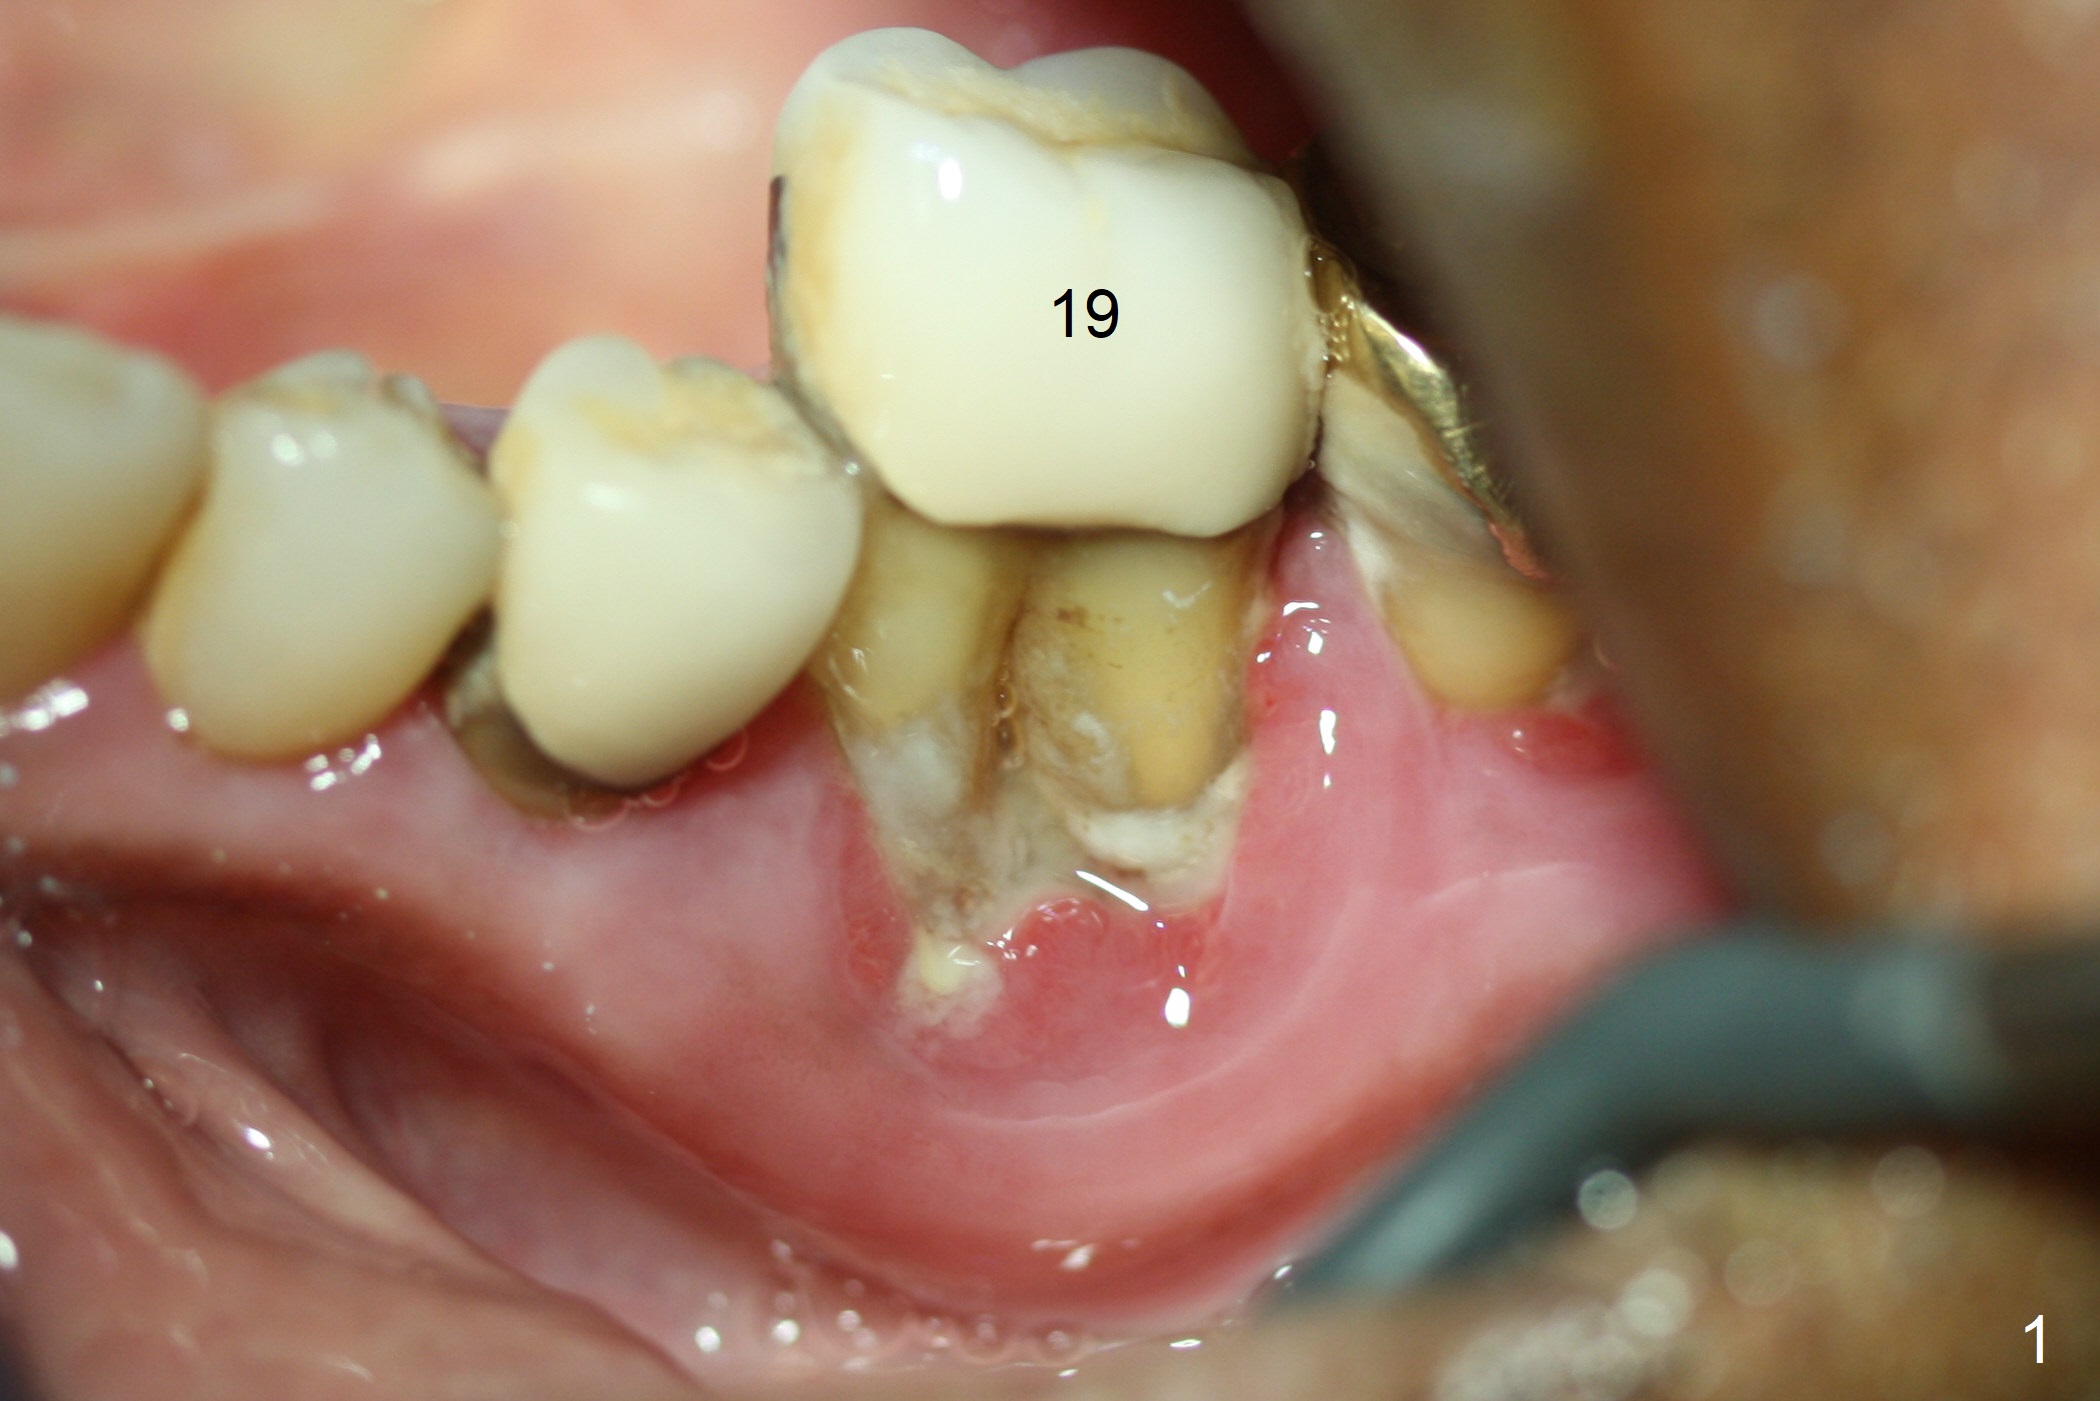

After extraction of the supraerupted tooth #19 with severe buccal gingival recession, the buccal and lingual plate are found to be lost. The sockets are fused and flat without the septum. The bone is hard and painful for the initial osteotomy with infiltration anesthesia (Fig.2). Following block anesthesia, the initial osteotomy depth extends to 8 mm (Fig.3,4). With apparent 4.9 mm clearance, the osteotomy is further extended to 10 mm. The osteotomy walls are apparently intact without severe hemorrhage after each drill. Due to the thick gingiva and severe bone loss, a 5x12 mm implant is intentionally placed 3 mm above the base of the socket bone (Fig.5,6 (yellow dashed line)). Vanilla Cortical and Cancellous allograft (Fig.6 *) is placed around the exposed implant and 7.8x5(6) mm abutment with 4 and 2 mm buccal and lingual gaps. Next collagen plug cut in strip is placed to fill the most coronal aspect of the socket (Fig.7 *). The buccal and lingual gingivae are approximated with sutures proximally. Finally periodontal dressing is applied. Since the Inferior Alveolar Canal is vague in intraop PAs (Fig.4,5), there is worry about potential nerve damage during and after osteotomy. This should be no issue if preop panoramic X-ray is reviewed with measurement (Fig.8). The bone graft appears to remain in place nearly 4 months postop (Fig.9). Two weeks later, he returns for impression. When the provisional is removed, the gingiva is unhealthy. Without the provisional and with improved oral hygiene, the gingiva is healthy one week later, but the tooth #18 is symptomatic. The latter is extracted with socket preservation (Fig.10 *). There is no apparent bone loss around the implant at #19 6.5 months post cementation (Fig.11).